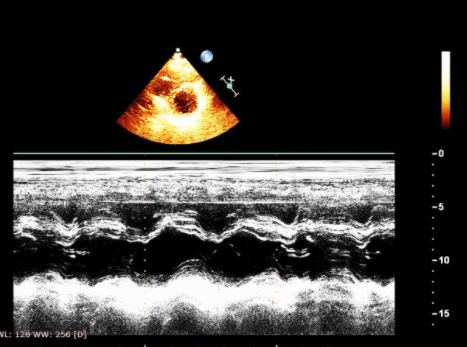

Помимо допплеровских изменений при ЭхоКГ можно выявить признаки нарушения диастолической функции левого желудочка в М- и В-режимах. В М-режиме при диастолической дисфункции снижаются наклон и скорость движения фиброзного кольца митрального клапана в фазу раннего диастолического наполнения левого желудочка. В М- и В-режимах увеличивается размер и объем левого предсердия. Обычно, хотя и не обязательно, выявляется увеличение толщины стенки и массы миокарда левого желудочка.

Линейный измерения ЛЖ и его стенок производятся в парастернальной позиции по длинной оси.

Измерения строго перпендикулярно длинной оси ЛЖ, чуть ниже уровня кончиков створок МтКл.

Внутренние размеры можно получить в 2D- и M-режиме; предпочтительный 2D-режим.